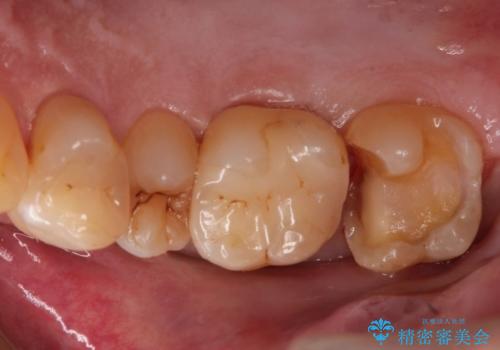

つめものが欠けた 奥歯のセラミックインレー

- つめものが欠けたとのことで、来院された患者様です。

レントゲンから虫歯が深いことが予想されたため、神経の処置が必要になる可能性を説明した上で、

白いもの希望とのことで、セラミックインレー修復を行う方針をたてました。

レントゲンから、虫歯が深いことが予想されたため、ラバーダムを使用して虫歯治療を行いました。

幸い、そこまで虫歯は深くなく、神経の処置は必要なかったため、

予定通り、セラミックインレー修復を行いました。